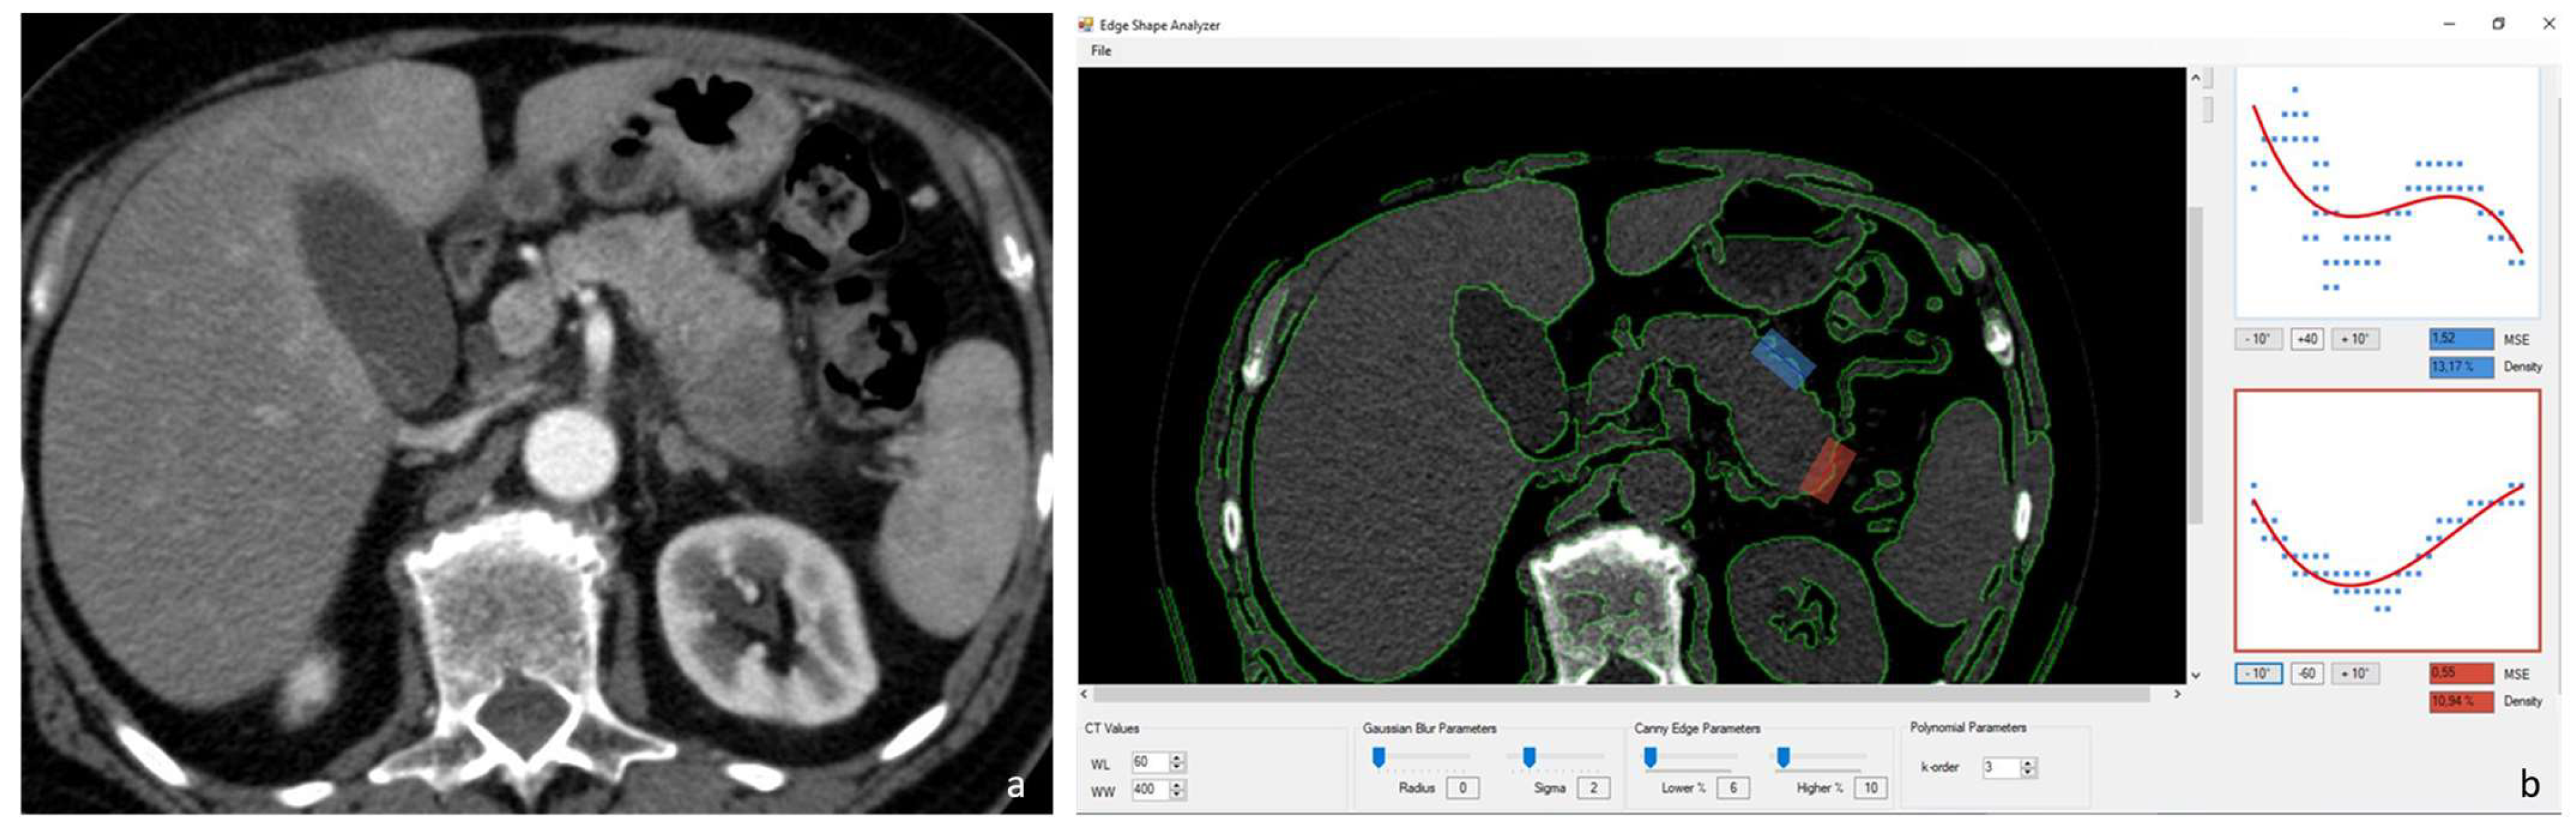

2.3. Image Analysis–Pancreatic Edge Analysis Software